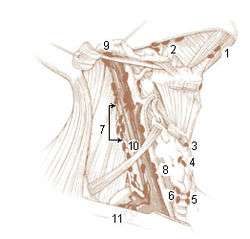

Deep Lymph Nodes 1. Submental 2. Submandibular (Submaxillary) Anterior Cervical Lymph Nodes (Deep) 3. Prelaryngeal 4. Thyroid 5. Pretracheal 6. Paratracheal Deep Cervical Lymph Nodes 7. Lateral jugular 8. Anterior jugular 9. Jugulodigastric Inferior Deep Cervical Lymph Nodes 10. Juguloomohyoid 11. Supraclavicular (scalene) | |

One system divides the nodes as follows:[4][5]

- Level I: Submental and submandibular nodes

- Level Ia: Submental - found between the anterior belly of the digastric muscles

- Level Ib: Submandibular triangle - found around submandibular glands in submandibular space

- Level II: Upper jugular nodes - Between posterior belly of digastric muscles superiorly and hyoid bone inferiorly

- Level IIa: Anterior, medial, lateral or posterior to internal jugular vein, or if posterior, must not have an intervening fat plane

- Level IIb: Posterior to internal jugular vein with fat plane between nodes and internal jugular vein

- Level III: Middle jugular nodes - between the hyoid bone and cricoid cartilage

- Level IV: Lower jugular nodes - between the cricoid cartilage and the clavicle

- Level V: Posterior cervical or spinal accessory nodes, posterior to the sternocleidomastoid muscle

- Level VA: Spinal accessory nodes from skull base to bottom of cricoid cartilage

- Level VB: Spinal accessory nodes between cricoid and clavicle

- Level VI: Visceral space lymph nodes - midline group of cervical nodes from hyoid to sternal manubrium, includes prelaryngeal, pretracheal, and paratracheal subgroups

- Level VII: Superior mediastinal nodes - between carotid arteries from top of manubrium superiorly to innominate vein inferiorly